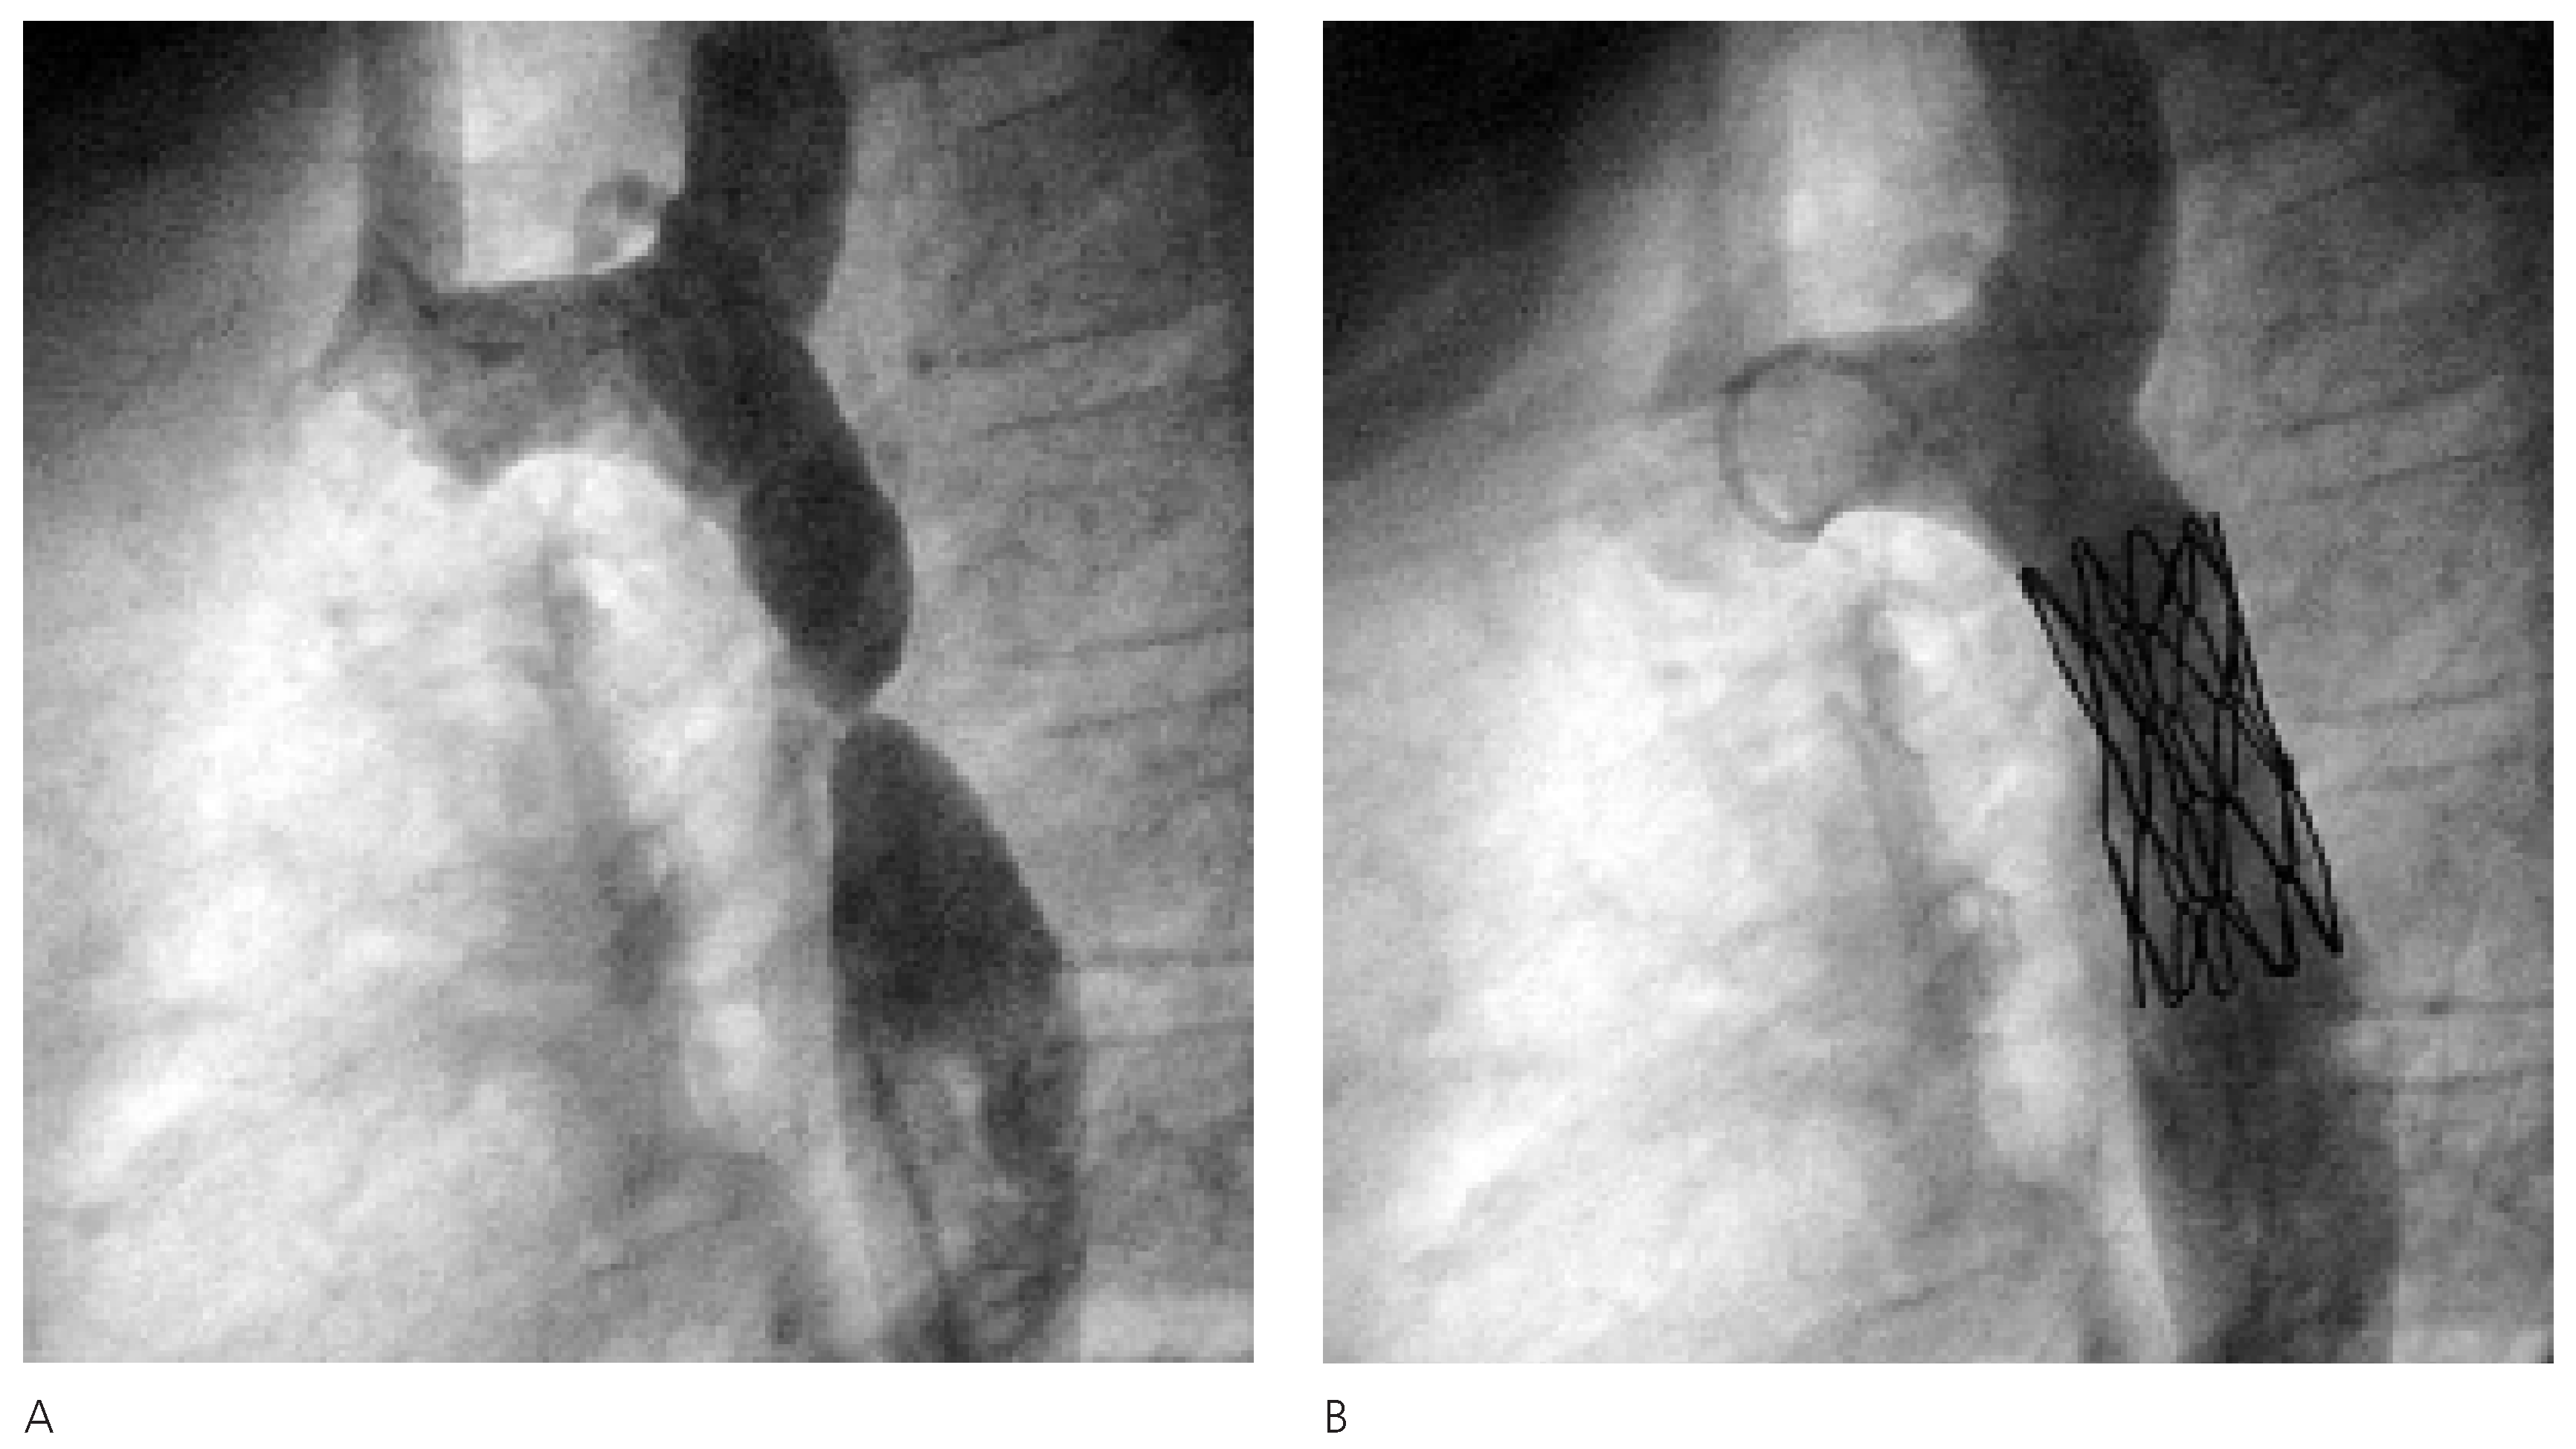

Echokardiographisch kam bis auf eine kompetente bikuspide Aortenklappe und eine leichte linksventrikuläre Hypertrophie ein strukturell normales Herz zur Darstellung. Die Aorta ascendens hingegen war mit 26 mm Durchmesser ektatisch, wobei der distale Aortenbogen sich auf 9 mm verjüngte. Der Aortenisthmusbereich distal der linken A. subclavia war echokardiographisch nicht einsehbar. Die kaum pulsierende Aorta abdominalis wies ein pathologisches systolodiastolisches Flussprofil (Figure 1) auf.

Figure 1. Typisches systolodiastolisches Flussprofil, gemessen dopplersonographisch in der proximalen Aorta descendens nach der Stenose. Die maximale Flussgeschwindigkeit von 380 cm/sec entspricht einem Druckgradienten von max/mean 60/20 mm Hg.